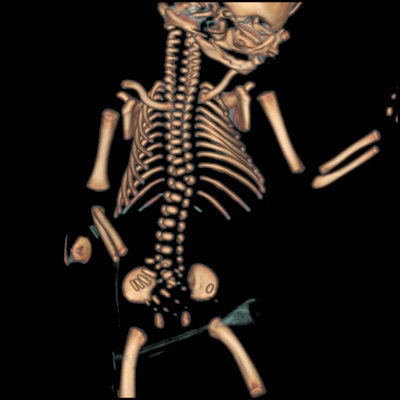

"While our preliminary scans did not detect all fetal abnormalities, some valuable information was obtained, and there are some features such as bony abnormalities, which can be difficult to elucidate at autopsy," they wrote.

Firstly, a high-definition helical scan was completed permitting the maximum spatial resolution possible for multiplanar bone and 3D volume rendered skeletal imaging (3D skeleton). This was followed by a dual energy acquisition. Both high and low energy (kVp) datasets were acquired simultaneously for near perfect anatomical registration.

Six fetuses were initially scanned. Three fetuses had been delivered after death in utero, and three were from pregnancies terminated due to fetal abnormalities. In all but one fetus, the crown-rump and crown-heel length measurements determined on CT were within 6% of the autopsy measurements. There was quite poor correlation between CT and autopsy measurements of the fetal foot length and head measurements, probably due to fetal positioning; the foot can be more easily "straightened" during a direct examination.